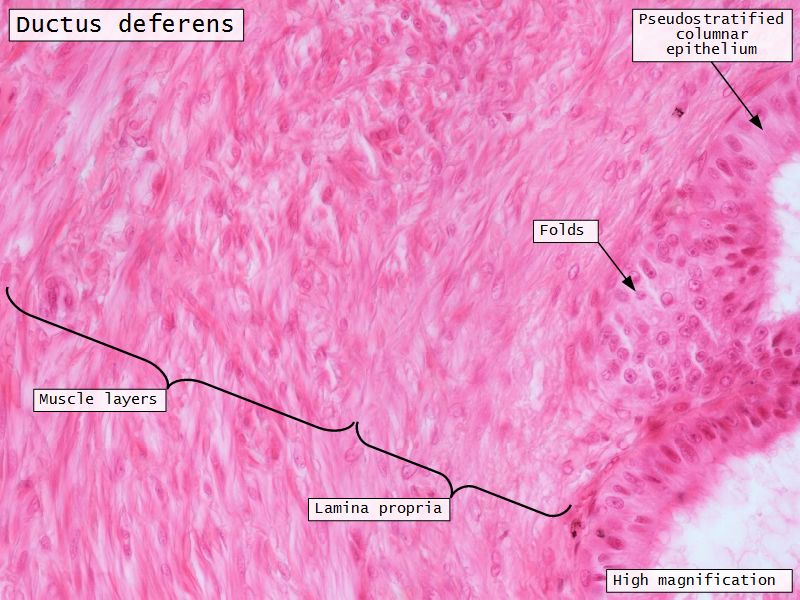

Ductus deferens

- Muscular duct with small lumen

- Lumen

- Pseudostratified columnar epithelium

- Fibroelastic lamina propria

- Muscle

- Inner longitudinal

- Middle circular

- Outer longitudinal

Ductus deferens

- Longitudinal folds in

- Epithelium

- Lamina propria